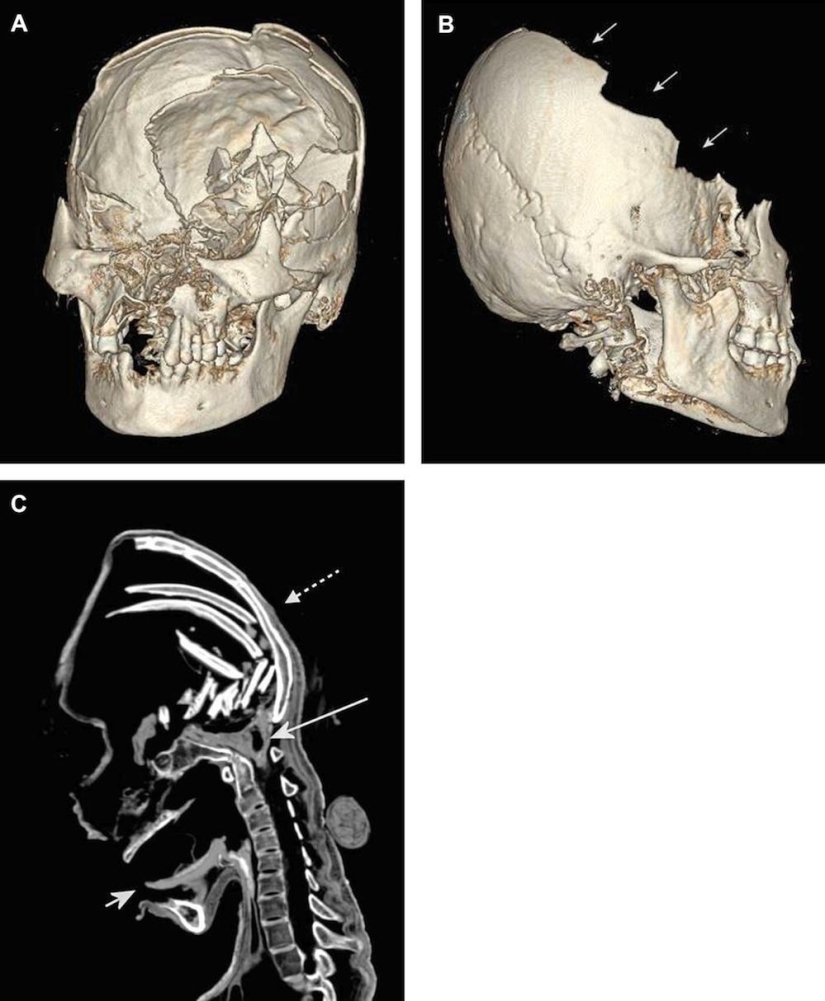

Por un lado, la cara de la momia parecía bastante normal, pero dentro de sus huesos del cráneo estaban rotos.

Como puedes ver, la parte frontal de su cráneo está completamente aplastada.